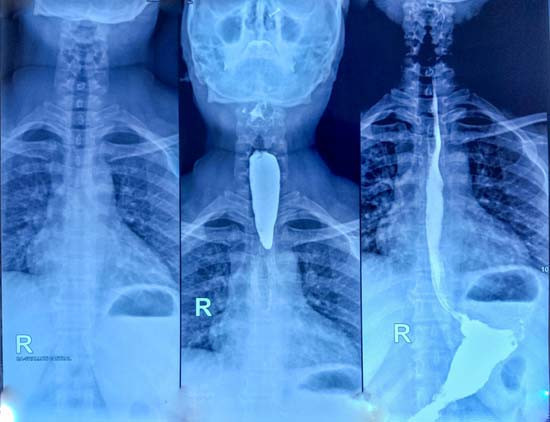

İkinci doktor bir sorun olduğunu anlamış olacak ki, iki hafta içinde endoskopi yapılması için randevu ayarladı. İşlem sırasında, yemek borusunda bir tıkanıklık olduğunu ekrandan Andrew kendi gözleriyle görebiliyordum.

Daha da korkutucu olanı, kamerayı bu engelin ötesine, midesine geçirememişlerdi. Andrew, sağlık ekibinin yüzündeki ifadeden bir şeylerin ters gittiğini anlamıştı. Panik içinde beklerken bir kanser destek hemşiresinin gelmesi istendi.

Tüm bu acıların ardından altı ay sonra doktor inanılmaz bir haber verdi: Tümör o kadar küçülmüştü ki lenf düğümlerinde neredeyse ölçülemez hale gelmişti. Yemek borusundaki tümör ise bir elma boyutundan ceviz boyutuna gerilemişti.

Bu başarı, Andrew’un artık ameliyat edilebileceği anlamına geliyordu; ‘özofajektomi’ yapılacaktı yani sağ akciğeri söndürülecek ve yemek borusunun yaklaşık 15 santimetrelik kısmı kesilip atılacaktı.